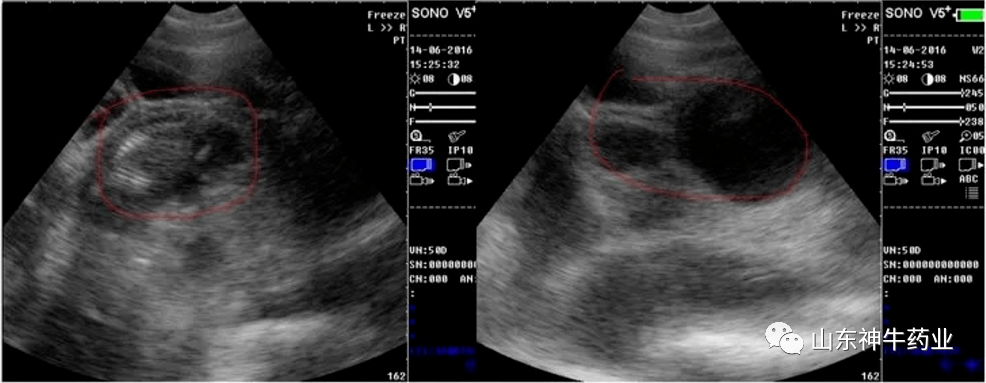

【技术】如何使用b超做好妊检工作!

图片尺寸986x383